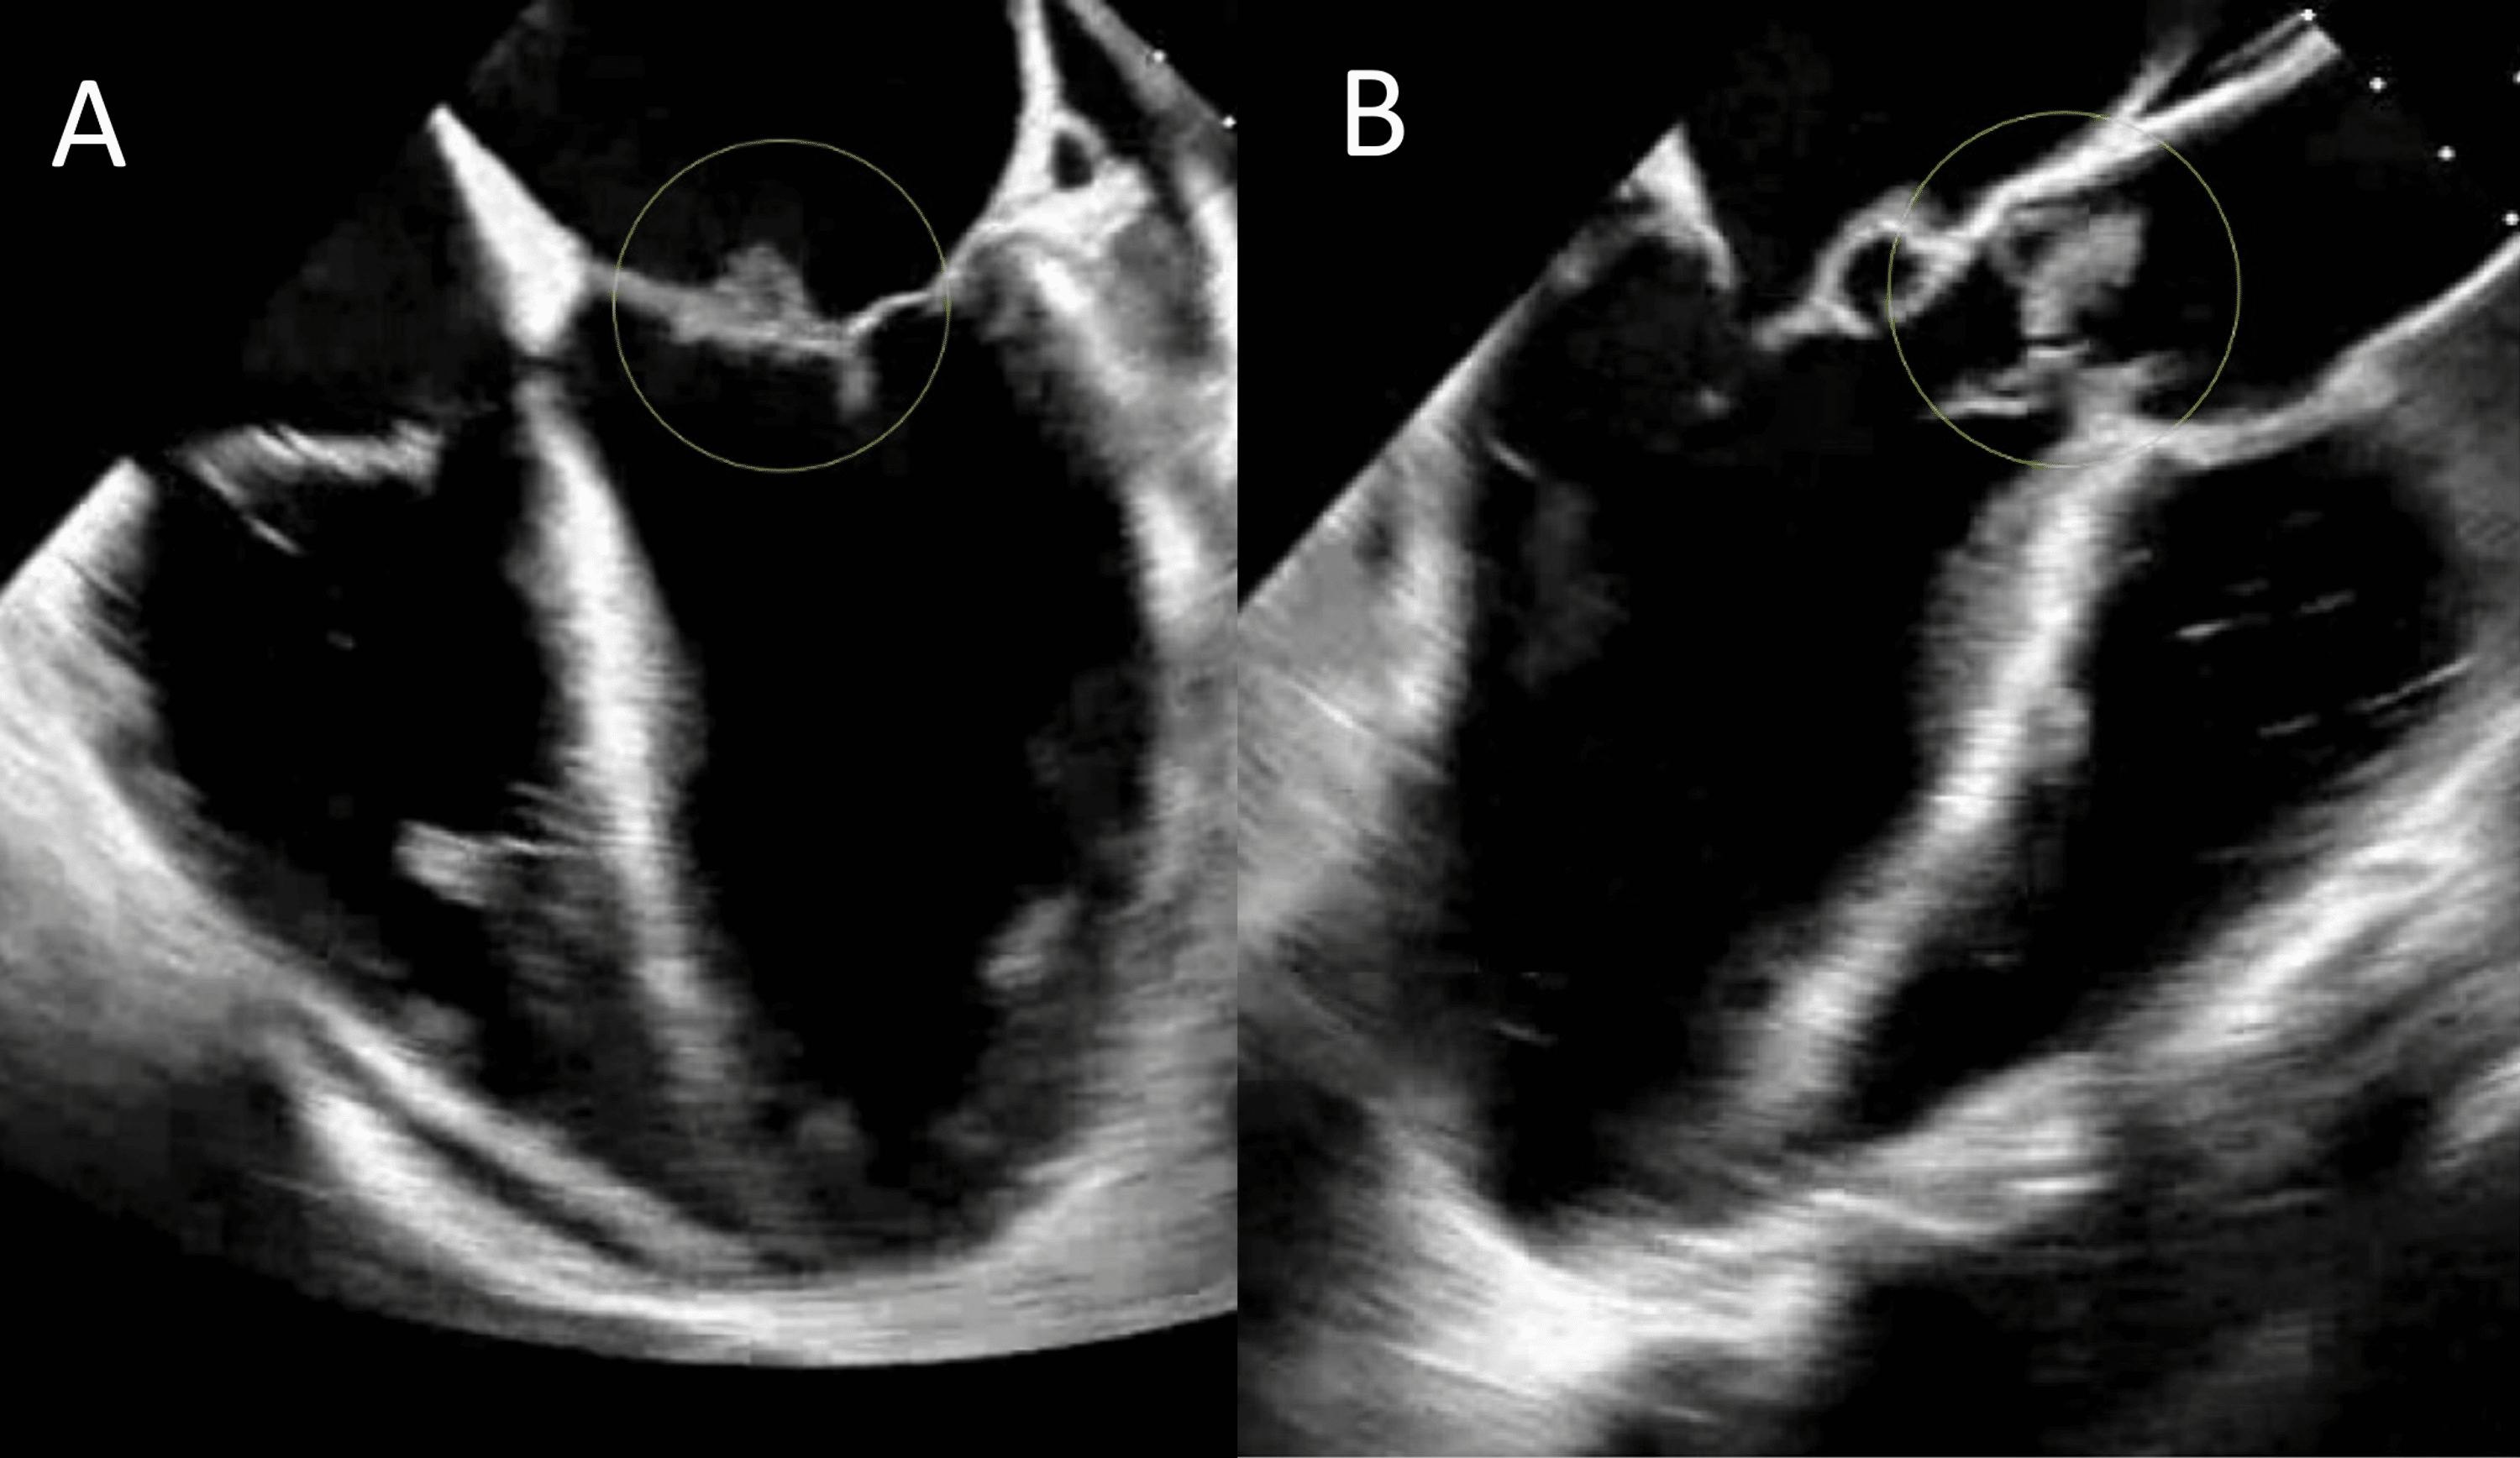

From www.researchgate.net

Right ventricular perforation. A A repeat 2D echocardiographic image What Happens When A Heart Valve Rupture In this condition, the valve between the left heart. papillary muscle rupture is one of the catastrophic mechanical complications following myocardial. mitral valve regurgitation is the most common type of heart valve disease. aortic valve damage (aortic regurgitation) or rupture into the lining around the heart (cardiac tamponade) prevention you can. Heart murmurs and valve problems. . What Happens When A Heart Valve Rupture.